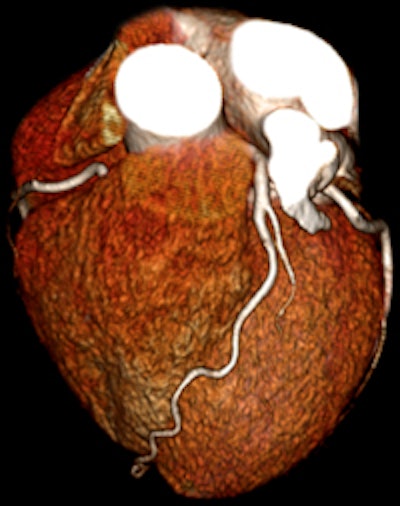

Toshiba's CT dose reduction efforts revolve around two technologies, adaptive iterative dose reduction (AIDR) and Target CTA. AIDR involves multiple iterative reconstructions to reduce radiation dose and improve image quality, while Target CTA makes use of the Aquilion One scanner's ability to scan the heart in one rotation to improve organ targeting and minimize padding of the scan range. The technique is most useful during gated cardiac studies.

| Low-dose prospective cardiac CTA image acquired in one gantry rotation on Aquilion One. |

The protocol can perform a pulmonary embolism scan in 2.3 seconds; whole-body scans can be performed in 3.1 seconds with a CT dose index volume (CTDIvol) of 7.5 mGy, compared to American College of Radiology (ACR) reference values of 25 mGy or less for abdominal scanning. The scanning mode is particularly well-suited for patients who have difficulty staying still during studies, such as trauma patients.